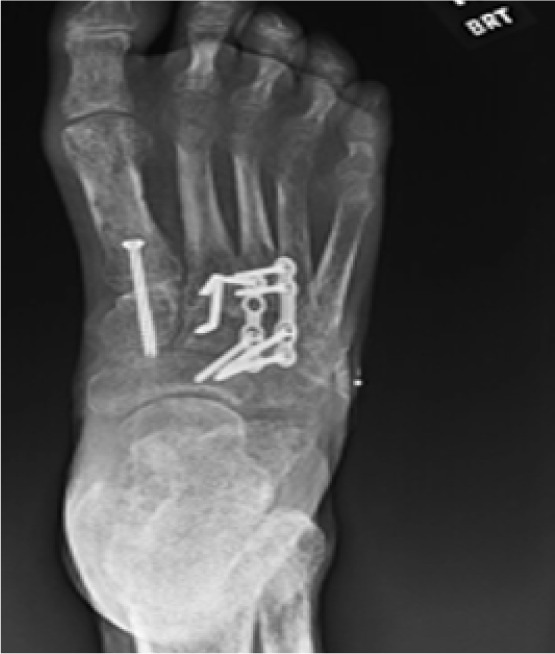

Following clinical resolution of infection, the second stage involved definitive deformity correction. A Lapidus bunionectomy with fusion of the first tarsometatarsal joint was performed to correct medial column instability and hallux valgus deformity. Concurrently, hammertoe corrections of the second through fifth digits were completed using arthrodesis techniques to address rigid digital contractures contributing to abnormal lateral forefoot pressure (Figure 11).

FIGURE 11 Postoperative image at 12 weeks showing healed lateral forefoot with corrected alignment.

In the third and final stage, elective removal of hardware was performed after radiographic evidence confirmed successful fusion and alignment (Figure 12). This was done to reduce long-term risk of hardware prominence or skin breakdown, particularly given the patient’s history of ulceration and peripheral neuropathy.

FIGURE 12 Radiograph confirming Lapidus fusion consolidation and digital realignment.